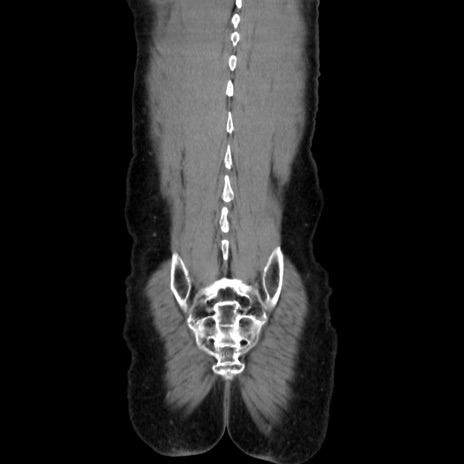

症例37(冠状断像)

【症例】40歳代 男性

【主訴】腹痛

【現病歴】4時間ほど前に電車に乗車中に臍部上より腹痛出現。徐々に増悪し起立困難となり、救急外来受診。生ものは数日食べていない。今朝お雑煮を食べた。

【身体所見】BT 36.8℃、BP 117/84mmHg、HR 91/min、SpO2 97%、苦悶様、腹部:臍上部広範囲圧痛あり、反跳痛±

【データ】WBC 8100、CRP 0.03